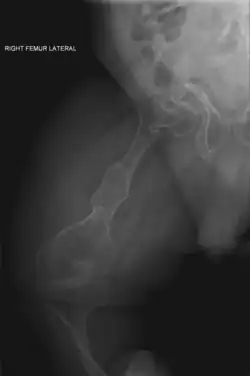

Right femur

Four X-rays of a 24-year-old American man (Fredrick Brennan), who had had more than one hundred bone fractures in his lifetime, and received a childhood clinical diagnosis of type IV–B OI. Genetic diagnosis in 2018 identified a previously uncatalogued pathogenic variant in the gene which encodes proα2(I) chains of type I procollagen, COL1A2, at exon 19, substitution c.974G>A. Due to childhood neglect and poverty, Brennan never received surgery to implant intramedullary rods. Malunions are evident as the humerus and femur were broken in adolescence, but orthopedic care did not follow. Severe scoliosis, as well as kyphosis, are also evident. The unavoidably low contrast in the film is due to a combination of Brennan's obesity and low bone mineral density (BMD). His BMD Z-score was -4.1 according to results of a dual-energy X-ray absorptiometry (DXA) scan also done in 2018.